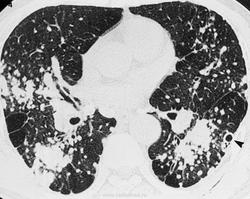

Во II стадии узелкового П. на фоне ячеистого рисунка выявляется обычно большое количество узелковых образований, покрывающих все легочное поле, но более часто расположенных в средних и нижних поясах. Диаметр узелков может достигать 5 и даже 10 мм. В участках наиболее густой концентрации узелков легочный рисунок перекрыт их тенями; видны лишь отдельные обрывки линейных теней. В связи с этим и корни легких выглядят как бы обрубленными. В базальных отделах легких отмечается буллезная эмфизема. Экскурсия диафрагмы ограничена. Имеются плевродиафрагмальные и плевроперикардиальные спайки.

В III стадии П. узелки сливаются между собой, образуя крупные узлы или конгломераты. Между узлами можно выявить кавернозные полости, участки цирроза. В базальных отделах легких - буллезная эмфизема. Лимфатические узлы корней легких и средостения заметно увеличены, в их толще имеются включения солей кальция. В части случаев обызвествление лимфатических узлов носит краевой скорлупообразный характер. Диафрагма деформирована, фиксирована. Реберно-диафрагмальные синусы облитерированы. Сердце легочное.